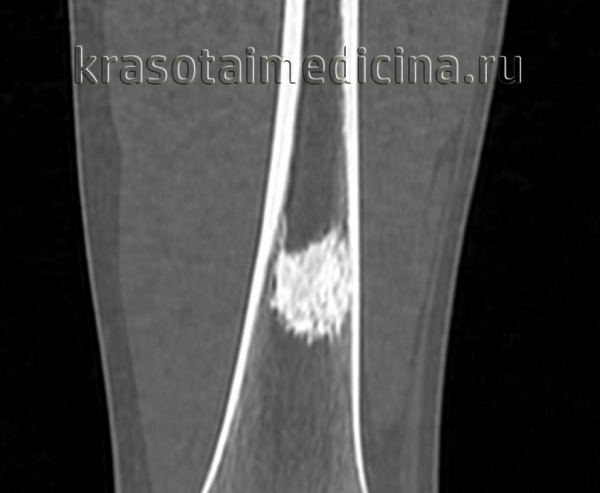

Рентгенограмма остеоид-остеомы проксимального отдела бедра. Имеется рентген-прозрачное образование с четкими контурами, окруженное склерозированной костью. Размеры прозрачного участка всегда меньше 1,5 см. Рентгенограмма голени в прямой проекции: остеоид-остеома малоберцовой кости. Обратите внимание на доброкачественный характер реакции кортикального слоя и увеличение объема кости. Остеоид-остеома диафиза бедра. Обратите внимание на утолщение кортикального слоя кости и доброкачественное периостальное новообразование костной ткани. Еще одним характерным признаком заболевания является интрамедуллярный склероз (стрелка). После рентгенографии методом выбора для диагностики остеоид-остеом является КТ, — очень чувствительный метод обнаружения при интра- и юкстакортикальном расположении «гнезда». Такое поражение сопровождается значительным утолщением кортикального слоя. Обратите внимание на случайное близкое расположение питающей артерии. Очень чувствительным методом диагностики остеоид-остеом является сцинтиграфия костей. В данном случае отмечается значительное усиление сигнала от пораженных дистальных отделов бедренных костей. Аксиальный КТ-срез (а) и взвешенный по Т2 МР-скан (б) с типичными признаками юкстакортикальной остеоид-остеомы дистального отдела бедра. На КТ виден типичный медуллярный склероз вокруг образования. На МРТ—выраженный сопутствующий отек костного мозга и периостальная реакция прилежащей надкостницы. Отечность проксимальной фаланги указательного пальца вследствие остеоид-остеомы. Интраоперационная картина «гнезда». Макропрепарат. «Гнездо» обычно имеет вишневокрасную окраску. При микроскопическом исследовании видны тонкие, хаотично расположенные остеоидные трабекулы, между трабекулами располагается богатая сосудами рыхлая соединительная ткань. При большем увеличении в веществе остеоида видны одинакового вида остеобласты без атипии ядер.

3. КТ при остеоид-остеоме:

• КТ эффективна для диагностики и уточнения локализации опухоли:

о Кортикальное расположение или субпериостальное или интрамедуллярное

• Сопряженная и/или удаленная склеротическая реакция

• Литический очаг ± центральная зона склероза

• К очагу часто примыкают питающие сосуды